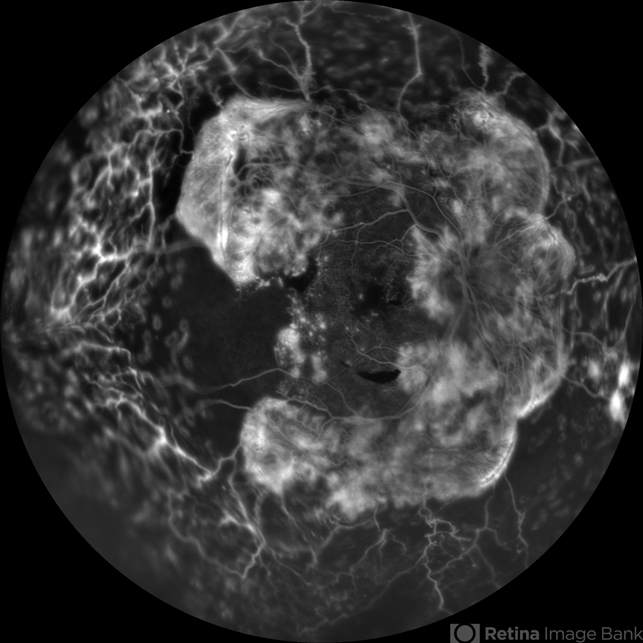

- proliferative diabetic retinopathy (PDR), choroidal effusion

- A 17-year-old juvenile diabetic patient came to us with extensive neovascular proliferations and PRP done a week back and had developed 360 degree choroidal effusion as seen in this wide field fluorescein angiography showing active leaking fronds and capillary non perfusion areas temporal to macula and choroidal effusion all around.